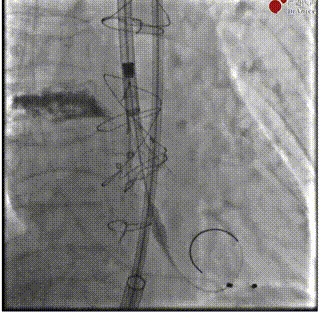

主动脉根部造影

20mm纽曼球囊预扩张

系统过弓时控制导丝避开主动脉弓部钙化。

递送系统过弓

Hat marker偏向影像左侧,符合对齐预测,C paddle位置的瓣膜对合柱将放置于左右冠开口之间,保留冠脉通路。

方向确认与预释放

瓣膜释放

瓣膜释放的前半段深度3mm,后半段受钙化挤压导致轻微下滑至5mm。

深度造影

释放前深度评估

释放后造影

导丝回退至鼻锥内释放张力避免鼻锥勾挂瓣膜。术中,Near Overlap体位下Hat marker轻微偏向右侧,确认C paddle应于左右冠脉开口中间,成功保留LCA与RCA通路。微量PVL,术后压差7mmHg;自体瓣环面瓣架呈椭圆状。环上瓣膜工作高度瓣架呈良好圆形,瓣膜开口面积良好。翻山造影确认主入路无严重血管并发症,手术结束。